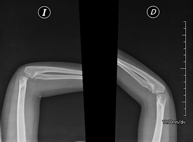

- Limb X-ray

This technique uses X-ray imaging to examine the limbs, especially the bones. Indicated for: trauma, joint infections.